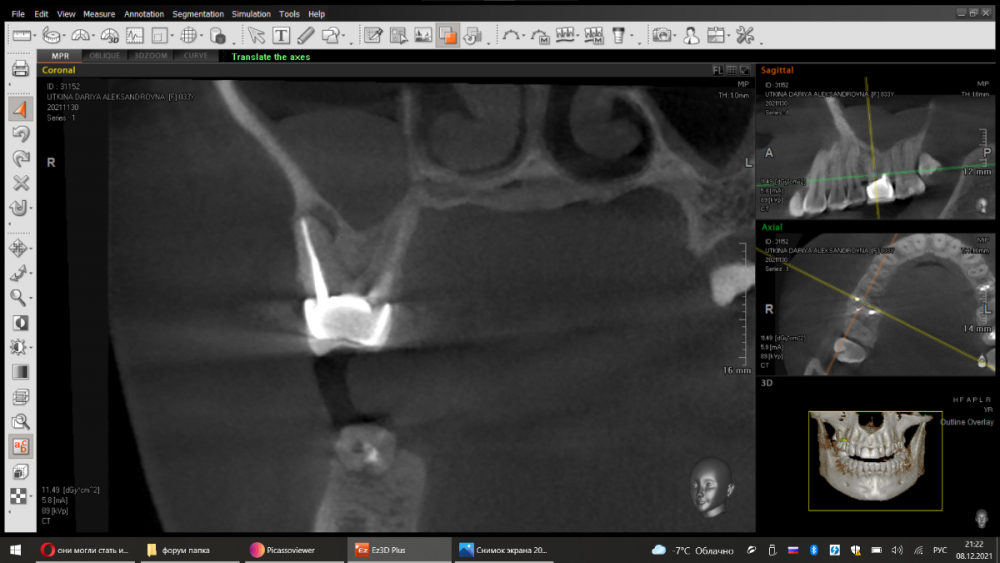

dentikl Опубликовано 7 декабря, 2021 Поделиться Опубликовано 7 декабря, 2021 Срезы кт через 6 месяцев терапии.Старый кальциевый протокол.Результат до постоянного пломбирования каналов. 3 Ссылка на комментарий

dentikl Опубликовано 7 декабря, 2021 Автор Поделиться Опубликовано 7 декабря, 2021 два клинических случая,смена кальция раз в три месяца,кт контроль.После значительного уменьшения дефектов следовало постоянное пломбирование каналов с последующей протетикой.Случай первый. 1,2 срез-до ,3,4- через 6 месяцев. Случай второй 5,6 срез-до,7,8-после. Ссылка на комментарий

Женька Опубликовано 8 декабря, 2021 Поделиться Опубликовано 8 декабря, 2021 @dentikl ну посмотрите как выглядят зубы, все светятся Также и импланты на КТ светятся. Ссылка на комментарий

dentikl Опубликовано 8 декабря, 2021 Автор Поделиться Опубликовано 8 декабря, 2021 на реконструкции лучше чем в проекциях можно оценить степень повреждения (и динамику). Ссылка на комментарий